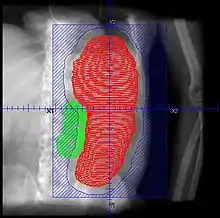

- No firm RT schedules, but low dose (<=1Gy) intermittent (2-3 fx/week), to total <=10 Gy recommended. One report suggests conventional 2 Gy/fx may be equally well tolerated. Consider dosing as follows (PMID 11230883 below):

- Patients should be continuously monitored, and fields adjusted with shrinking spleen

- RT should be stopped when therapeutic goal is achieved, rather than when prescription is reached

- Retrospective. 22 courses for 19 patients. Total dose 1.5 - 8.0 Gy (median 4.5 Gy), fractional dose 0.25 - 1 Gy delivered weekly or twice weekly. AP/PA. Median field reduction 25%

- Retrospective. 22 patients with 32 courses of SI. RT 0.25 - 0.5 Gy/fx, fields AP/PA and decreased with response, treatment halted with response